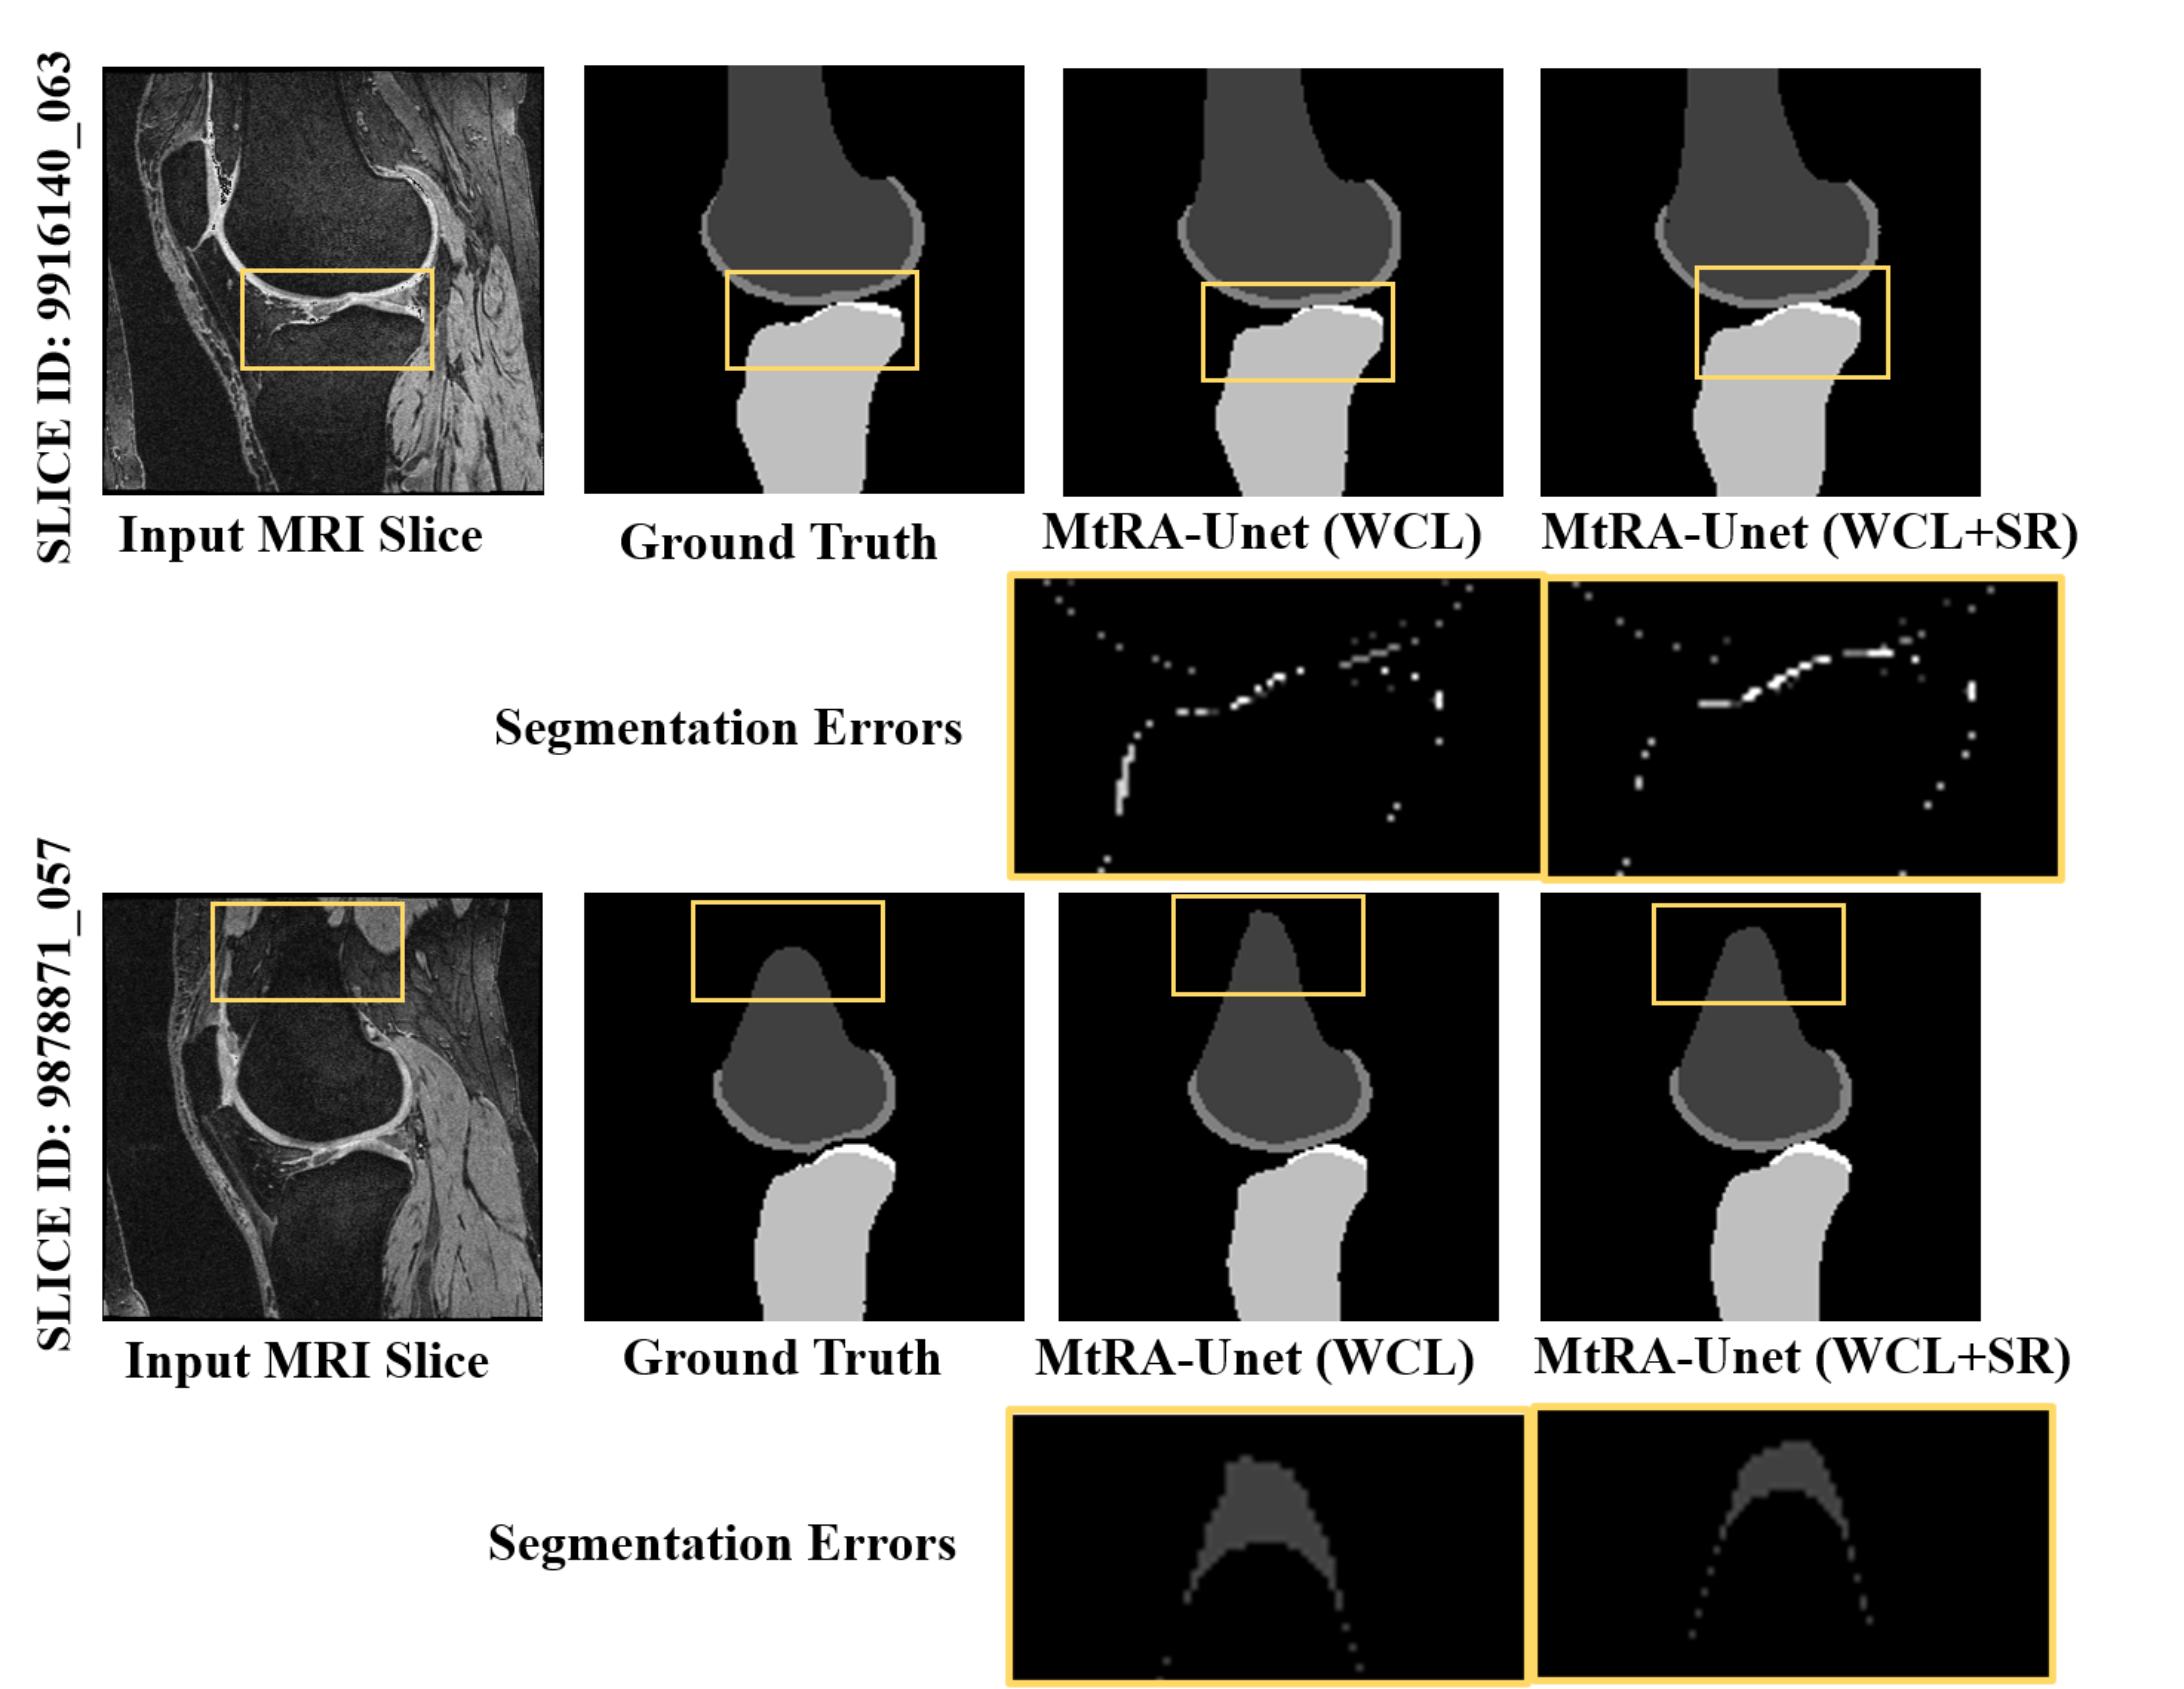

The experiment is conducted on the MtRA-Unet model for a variety of loss function weights as indicated in Table 8. It is observed that the optimal settings for η𝜂\eta and γ𝛾\gamma are 0.3 and 0.7 respectively. The significance of using SRL is confirmed by qualitative analysis with segmentation error maps of the tibia and femur which indicate lower segmentation error for a tibial and femoral region for MtRA-Unet with WCL+SRL as compared to the MtRA-Unet model with WCL as shown in Figure 9. But, it is observed that the higher weight for SRL resulted in a poor model’s performance with a decrease of 1% of average DSC over the optimal network setting.

Refer to caption

Figure 9: Visualization of qualitative results of the proposed MtRA-Unet model with and without shape reconstruction loss (SRL) function for femur and tibia (SLICE ID: 9916140_063 and 9878871_057)